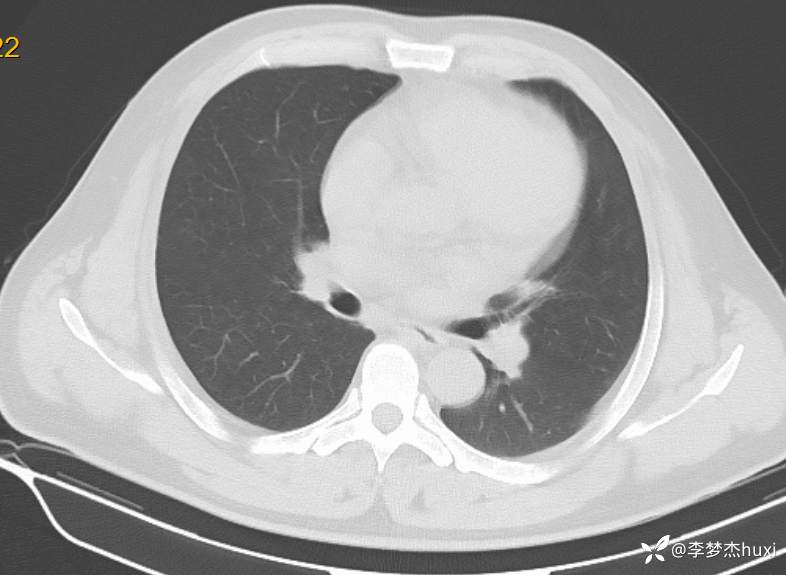

男性51岁,乏力伴胸闷、憋气4天入院,诊断可以秒杀且过目不忘

男, 51 岁,主因乏力伴胸闷、憋气4天于2024-06-11 11:57入院。

1.现病史:患者中年 男,患者缘于入院前4天无明显诱因出现乏力,伴胸闷、憋气,无咳嗽,咳痰,无发热,无咽痒,无咯血,无鼻塞、流涕,无发热,无恶心、呕吐,无腹痛、腹泻,无尿频、尿急、尿痛,无血尿及腰背部疼痛,院外查血常规:白细胞数目11.52x109/L,中性粒细胞百分比79.9%,血红蛋白69g/L。院外未服药治疗,症状无好转,现为求进一步诊治来诊,查肝胆胰脾肾彩超:脂肪肝(轻度),脾大。急诊以“低色素性贫血”收住院。。

患者诊断什么病?

精准诊断?